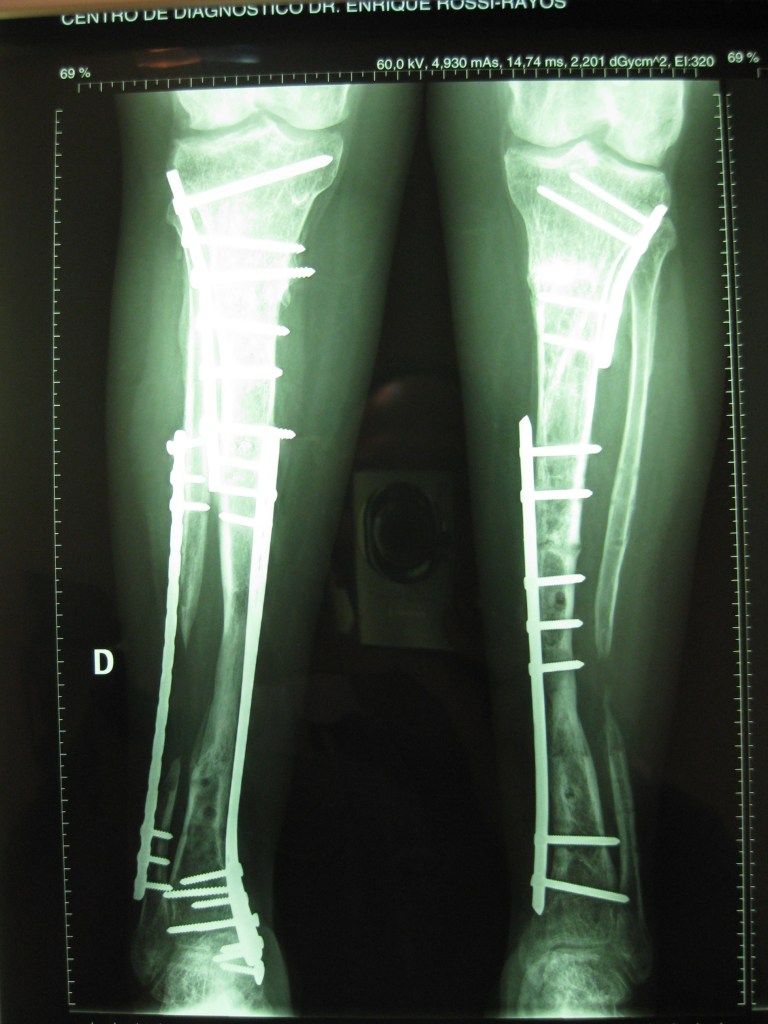

Infección y deformidad en tobillo y pie mas acortamiento óseo de pierna

Luego de varios años y cirugías sufridas por un accidente en moto, mi pie y pierna presentaban una gran deformidad asociada a una osteomielitis .

En mi provincia Chubut no podían tratarme más y solo me ofrecían la amputación

Tras viajar a BS AS y tener una consulta personal con el Dr Dratewka y Equipo en Cotram me realizaron estudios de imágenes y explicaron las posibilidades de Reconstrucción y evitar así la amputación

No solo trataron mi infección sino que corrigieron mi pie y me alargaron la pierna para poder caminar sin dificultades